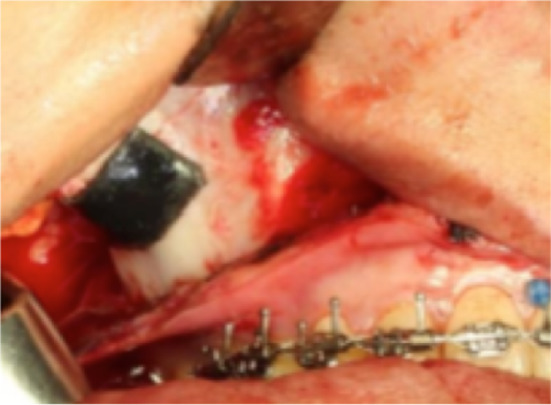

In order to have adequate access to the orbital floor, a transconjunctival approach is used. This approach has the benefit of leaving no facial scars. For a faster access and diminishing surgical time, a transconjunctival approach with a 15 mm. Mustarde canthotomy is another option but transconjunctival approach with extension through the union of the edges increases the risk of leaving a noticeable scar at the level of the outer edge of the eyelid. The osteotomy goes through the orbital floor in its anterior portion. It is initiated over the zygomatic bone, 5 mm anterior to the inferior orbital fissure as shown by the blue arrow in (Fig. 6). The surgical guide is placed over the zygomatic bone, and the osteotomy is completed (Fig. 6a, b).

Fig. 6.

a The osteotomy is drawn with a pencil. b The osteotomy is performed after placing the surgical guide